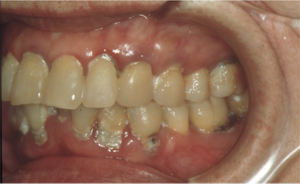

図7 器質的口腔ケアの効果(術前)

70歳代、女性、多量のプラークと著しい発赤・腫脹・口臭が見られた。口腔ケアを開始する前の口腔衛生状態と歯肉炎の状態。多量の歯垢(バイオフィルム)と進行した歯肉炎が認められる。